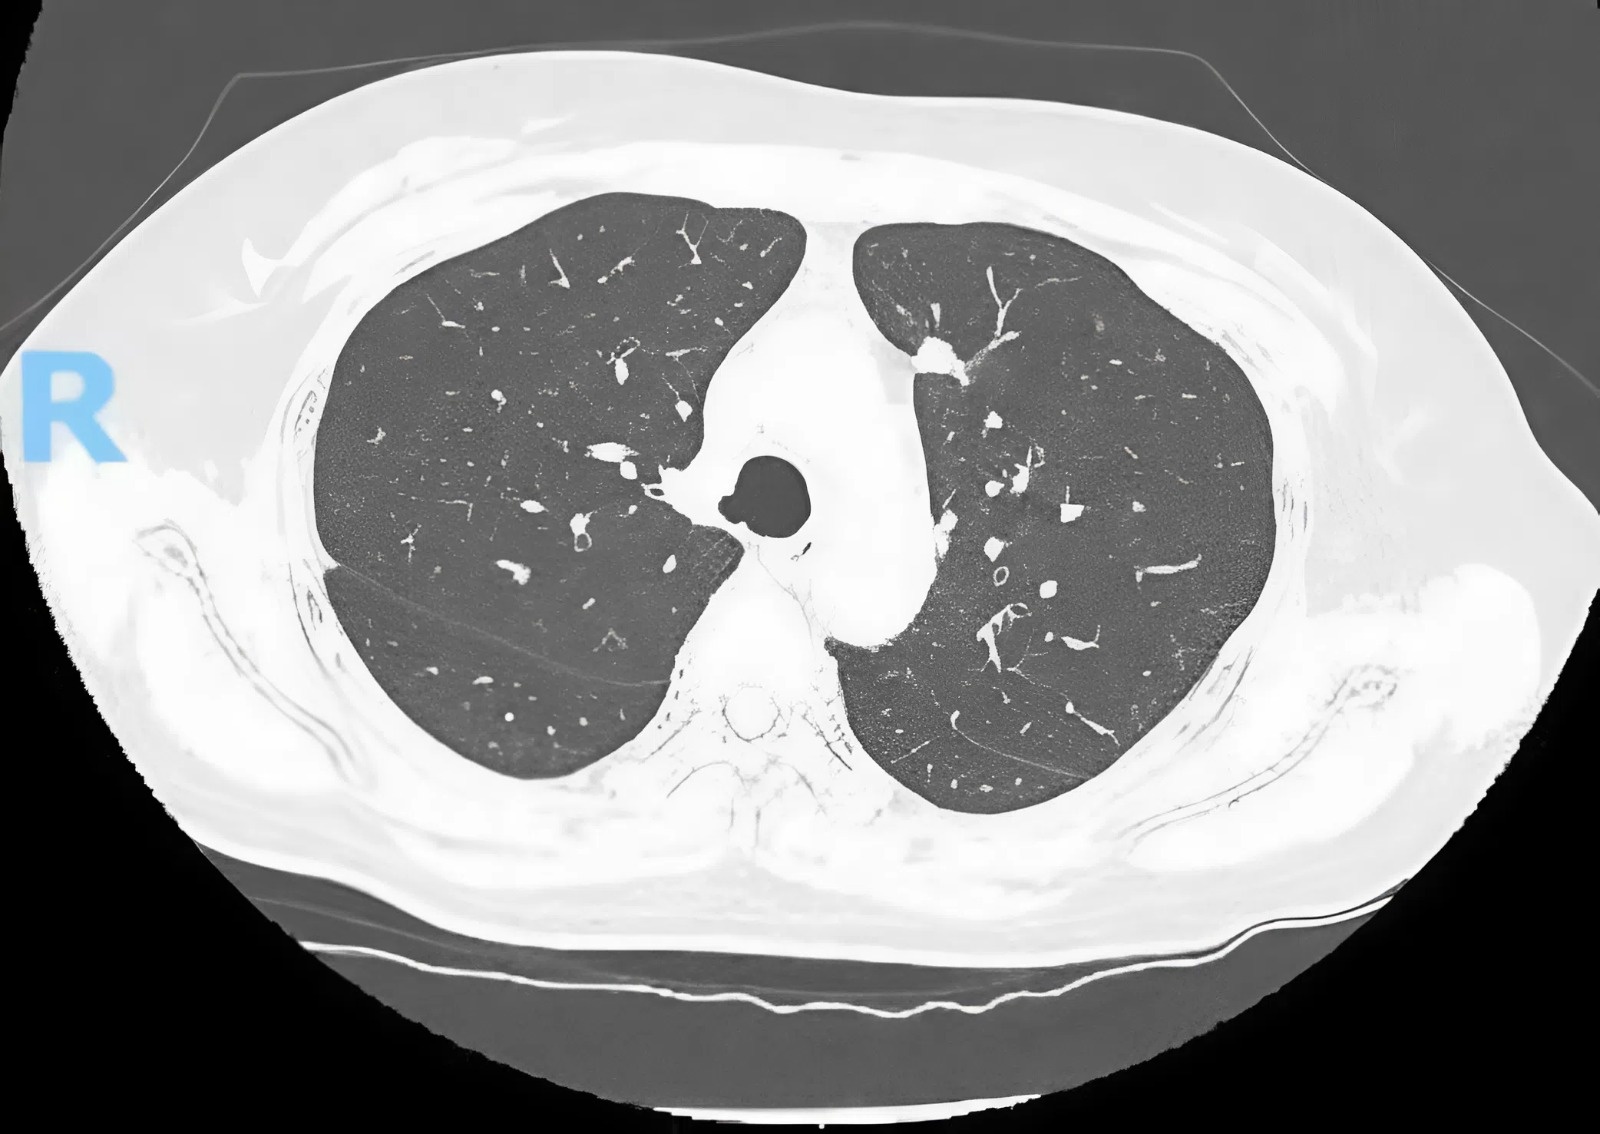

Sau khi được chẩn đoán ung thư amidan, bác sĩ tiếp tục phát hiện người đàn ông quê Nam Định bị hẹp khít van động mạch chủ. Đây là căn bệnh có tỷ lệ tử vong trong 2 năm lên tới 50%.

Hai tháng gần đây, ông Trần Anh Đức (66 tuổi, Nam Định) xuất hiện tình trạng nuốt khó. Các triệu chứng tăng nặng kèm theo mệt mỏi khi gắng sức. Ông Đức đến Bệnh viện Tai mũi họng Trung ương (Hà Nội) thăm khám và được chẩn đoán ung thư amidan.

Bệnh nhân có chỉ định phẫu thuật cắt amidan kết hợp nạo vét hạch. Trong quá trình làm xét nghiệm đánh giá trước mổ, các bác sĩ phát hiện bệnh nhân bị hẹp khít van động mạch chủ, chỉ định chuyển tuyến sang Viện Tim mạch Quốc gia, Bệnh viện Bạch Mai để can thiệp.

Đối với bệnh lý hẹp khít động mạch chủ, sau khi bàn bạc và thống nhất, gia đình bệnh nhân Đức chọn phương án thay van động mạch chủ qua ống thông (TAVI). PGS.TS Phạm Mạnh Hùng, Viện trưởng Viện Tim mạch Quốc gia, trưởng kíp phẫu thuật, cho biết điều đặc biệt trong ca can thiệp này là bệnh nhân bị ung thư amidan. Vì vậy, để đảm bảo an toàn và sức khỏe cho bệnh nhân, kíp can thiệp quyết định gây tê tại chỗ kết hợp an thần thay vì gây mê như thường lệ.

Hẹp van động mạch chủ do thoái hoá van là bệnh lý phổ biến ở người cao tuổi. Biểu hiện lâm sàng chủ yếu là mệt, giảm khả năng gắng sức, đau ngực, khó thở. Hẹp van động mạch chủ khi đã biểu hiện triệu chứng thường có tiên lượng nặng nề, với tỷ lệ tử vong trong 2 năm lên tới 50%.